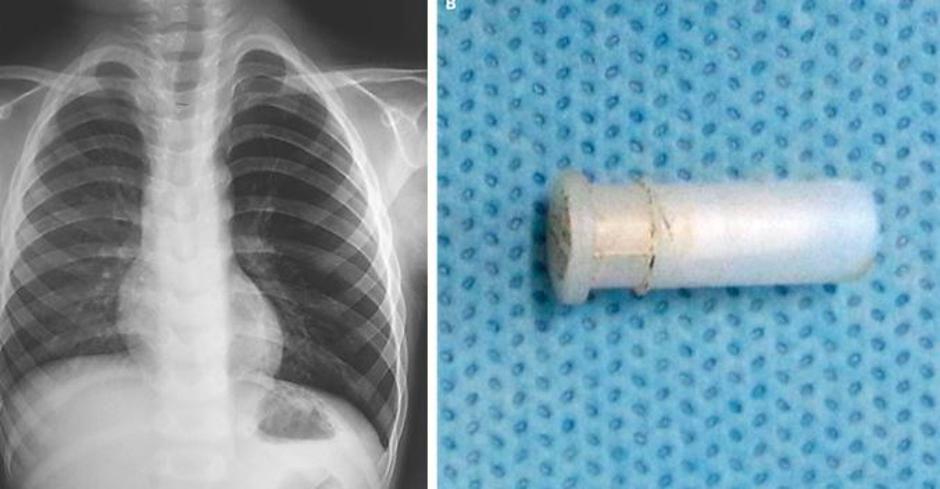

O podobnem primeru so v reviji poročali leto dni nazaj, ko se je  47- letni kadilec odpravil k zdravniku, ker je kar naenkrat začel izkašljevati rumeno sluz. Pričakoval je diagnozo raka na pljučih.

Rentgenska preiskava je pokazala na veliko senco, po temeljitem pregledu pa so zdravniki ugotovili, da ima moški v pljučih stožec. Šlo je pravzaprav za igračo oziroma prometni stožec iz kompleta igrač znanega proizvajalca igrač Playmobil. Moški se je pozneje spomnil, da je to igračo dobil kot darilo za svoj sedmi rojstni dan.